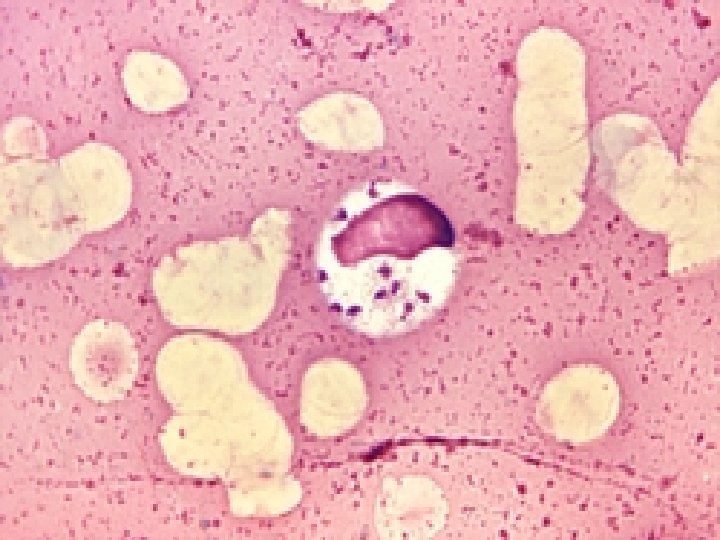

VISCERAL LEISHMANIASIS � � � Definitive diagnosis is made by observing the parasite (more specifically, amastigotes in tissue) on stained Giemsa smears or by observing the culture of bone marrow, splenic, hepatic, or lymph node aspirates. The most sensitive method is splenic puncture, although iatrogenic complications can be serious. Cultures are grown on NNN medium (media available from the CDC), a biphasic medium, or liquid media with fetal calf serum (eg, Schneider Drosophila medium). Culture grows for 1 -3 weeks. Serologic testing is useful with the indirect fluorescent antibody test (IFAT), which is 80 -100% sensitive in patients with visceral leishmaniasis who are not infected with HIV. IFAT may crossreact in patients who have leprosy, tuberculosis, malaria, schistosomiasis, Chagas disease, and African trypanosomiasis.